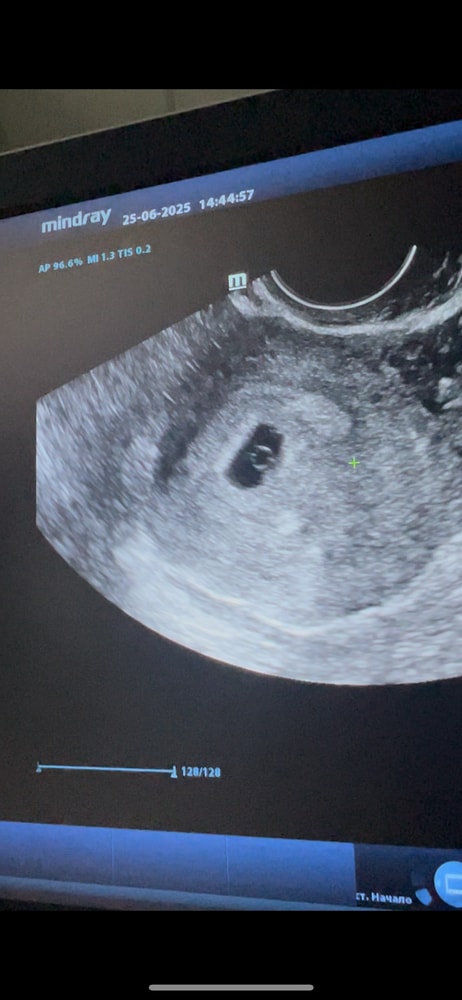

УЗИ 4-5 недель

Беременность I триместрПодросли за 10 дней,теперь сказали недельки через 2 придти,смотреть сердечко)Признаков особо у меня нет никаких,грудь только увеличилась очень и болит,но уже не так как в самом начале)